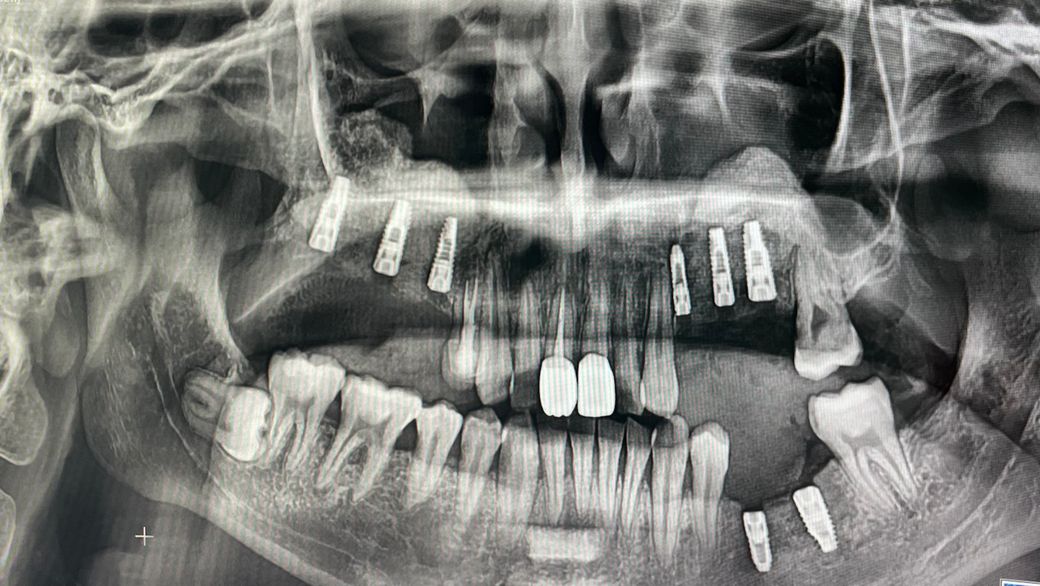

일단 여러 치료과정 중의 파노라마 사진이라 치료가 된 부분도 있고 아닌 부분도 있지만(하악 픽스쳐 밑 염증치료완료) 질문 드리고싶은 내용은 임플란트 식립부위의 이야기입니다.

양쪽 상악 어금니는 전부 임플란트를 하고 아래에도 몇개 하고있습니다만

• 1번 째 사진